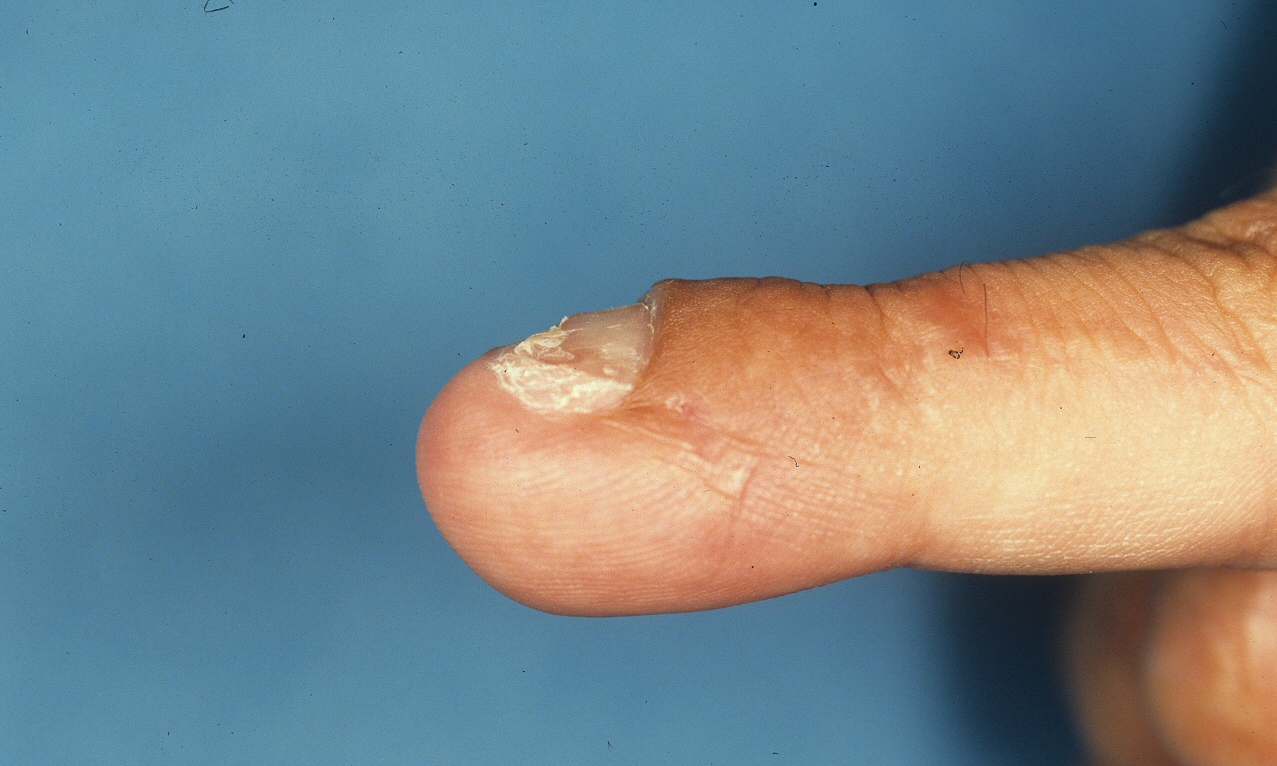

Case 1. This patient had an unstable small fingertip following a saw injury which resulted in loss of the central half of the distal phalanx of the small finger.

A palatal expansion clamp with a turnbuckle mechanism was used to design a progressively lengthening external fixator to restore length of the distal phalanx before reconstruction with a bone graft, here shown on a plastic sawbone model. This device is available at http://www.greatlakesortho.com and other orthodontic supplier retailers (no commercial interest).